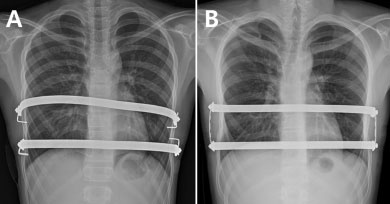

Á¤Áø¿ë ±³¼öÆÀÀº ±âÁ¸ 2°³ÀÇ ±³Á¤ ¸·´ë¸¦ °³º°ÀûÀ¸·Î °íÁ¤ÇÏ´Â ‘ºÐ¸®°íÁ¤ ¼ö¼ú¹ý’(»çÁøA)°ú, °¢ ±³Á¤ ¸·´ë ¾ç ³¡À» ÀÛÀº ±Ý¼Ó ¸·´ë·Î ¿¬°áÇØ »ç°¢Çü ÇüÅ·Π°íÁ¤ÇÏ´Â ‘»ç°¢°íÁ¤ ¼ö¼ú¹ý’(»çÁøB)ÀÇ °á°ú¸¦ ºñ±³ ºÐ¼®Çß´Ù.

ÀÇ·áÁøÀº 2011³â 9¿ùºÎÅÍ 2016³â 1¿ù±îÁö 2°³ÀÇ ±Ý¼Ó¸·´ë¸¦ »ðÀÔÇÑ ³Ê½º¼ö¼ú ȯÀÚ 86¸íÀ» ±³Á¤ ¸·´ëÀÇ ¾çÂÊ Ãø¸éÀ» °¢°¢ °íÁ¤ÇÑ A±º(44¸í, »çÁøA)°ú °¢ ±³Á¤ ¸·´ë¸¦ ¼¼·ÎÇü ¸·´ë¿Í ¿¬°áÇØ »ç°¢Çü ÇüÅ·Π°íÁ¤ ½ÃŲ B±º(42¸í, »çÁøB)À¸·Î ³ª´³´Ù.